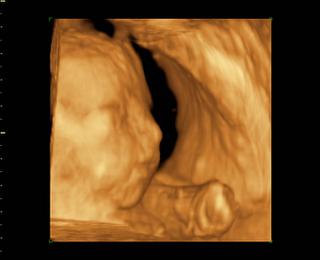

@14petulka88 Ja som pri prvom za fotky neplatila lebo som platila 1500 Sk za DVDčko, mám dve DVDčka jedno z 34 týždňa a jedno z 34t ýždňa. Tu len tak na ukážku dve fotky môjho Danielka z 3Dčka.